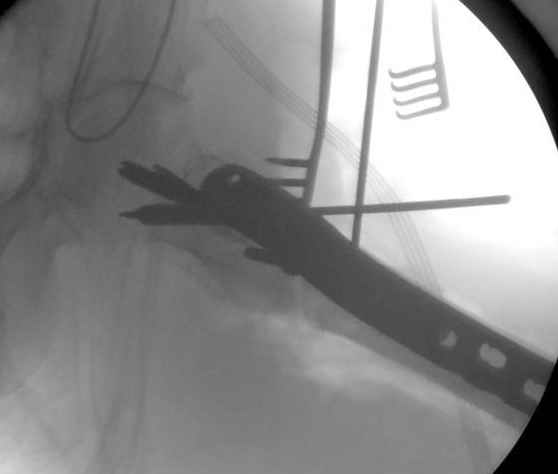

Re: [1/3] Перелом проксимального бедра

Применили проксимальную Synthes Locking plate, из-за множественных фрагментов посчитали более приемлемым в этом случае (клиника университетская, резиденты должны имет возможность созерцать разные варианты остеосинтеза).

Также старался минимизировать доступ на уровне перелома с субвастус доступом, диафиз фиксирован перкутанно, не стали гонятся за малым вертелом, как смог зафиксировал.

Перелом из четырех фрагментов, не стабильный (лекция Michael R. Baumgaertner, http://www.hwbf.org/ota/bfc/baumg/exp.htm), нужна стабильная фиксация.

Фиксация таких нестабильных чрезвертельных и reverse obliquity субтрохантерик переломов всегда была сложной задачей и ранее использовали Blade Plate. Но многие локальные общие ортопеды, к которым, в основном поступают такие больные, имели трудности с применением импланта, где необходимо было точная калькуляция по введению Blade и поэтому Synthes разработал Proximal Locking plate как альтернативу, где три проксимальные шурупа в разных направлениях создают концепцию угловой стабильности Blade Plate.